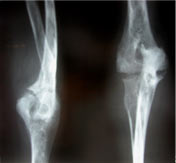

Koch's elbow